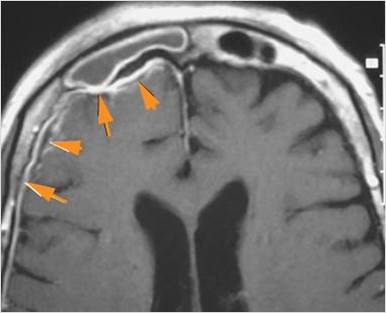

There is a subdural fluid collection or abscess along the boney walls of the anterior or middle cranial fossa.

There is a subdural fluid collection or abscess along the falx cerebri or within the tentorium.